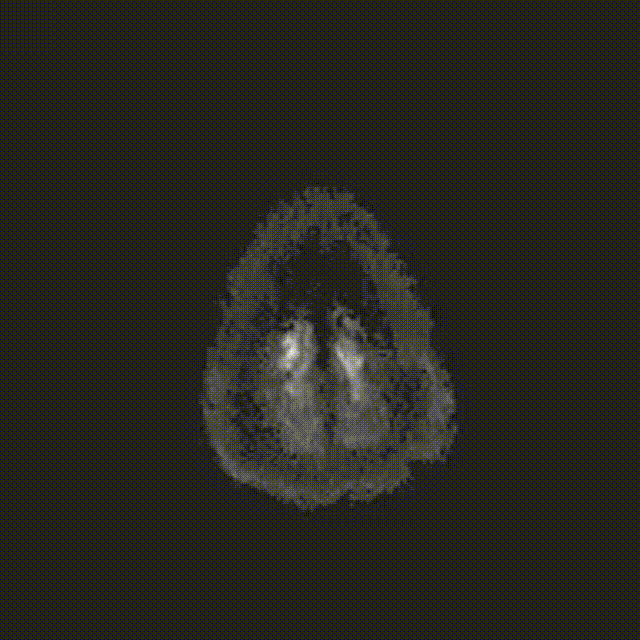

图6. A为患者术后1天CT平扫;B为患者术后5天CT平扫;C为患者术后5天DWI影像,可见大脑皮层、小脑、脑干散在新发梗塞灶。